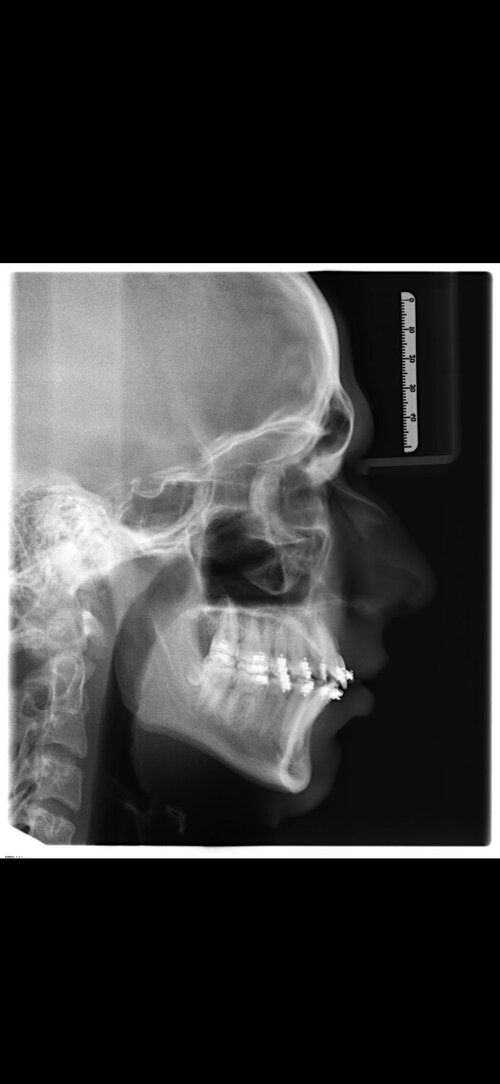

I'm getting bimax + genioplasty surgery in 3 days at 17 years old. I'm getting it performed by Dr Kater (Frankfurt am Main, Germany), he's very experienced but rather conservative with his movements so i won't get anything above 7 - 8mm movements. My question is how much of an ascend can I expect realistically? My occlusion is already pretty good.